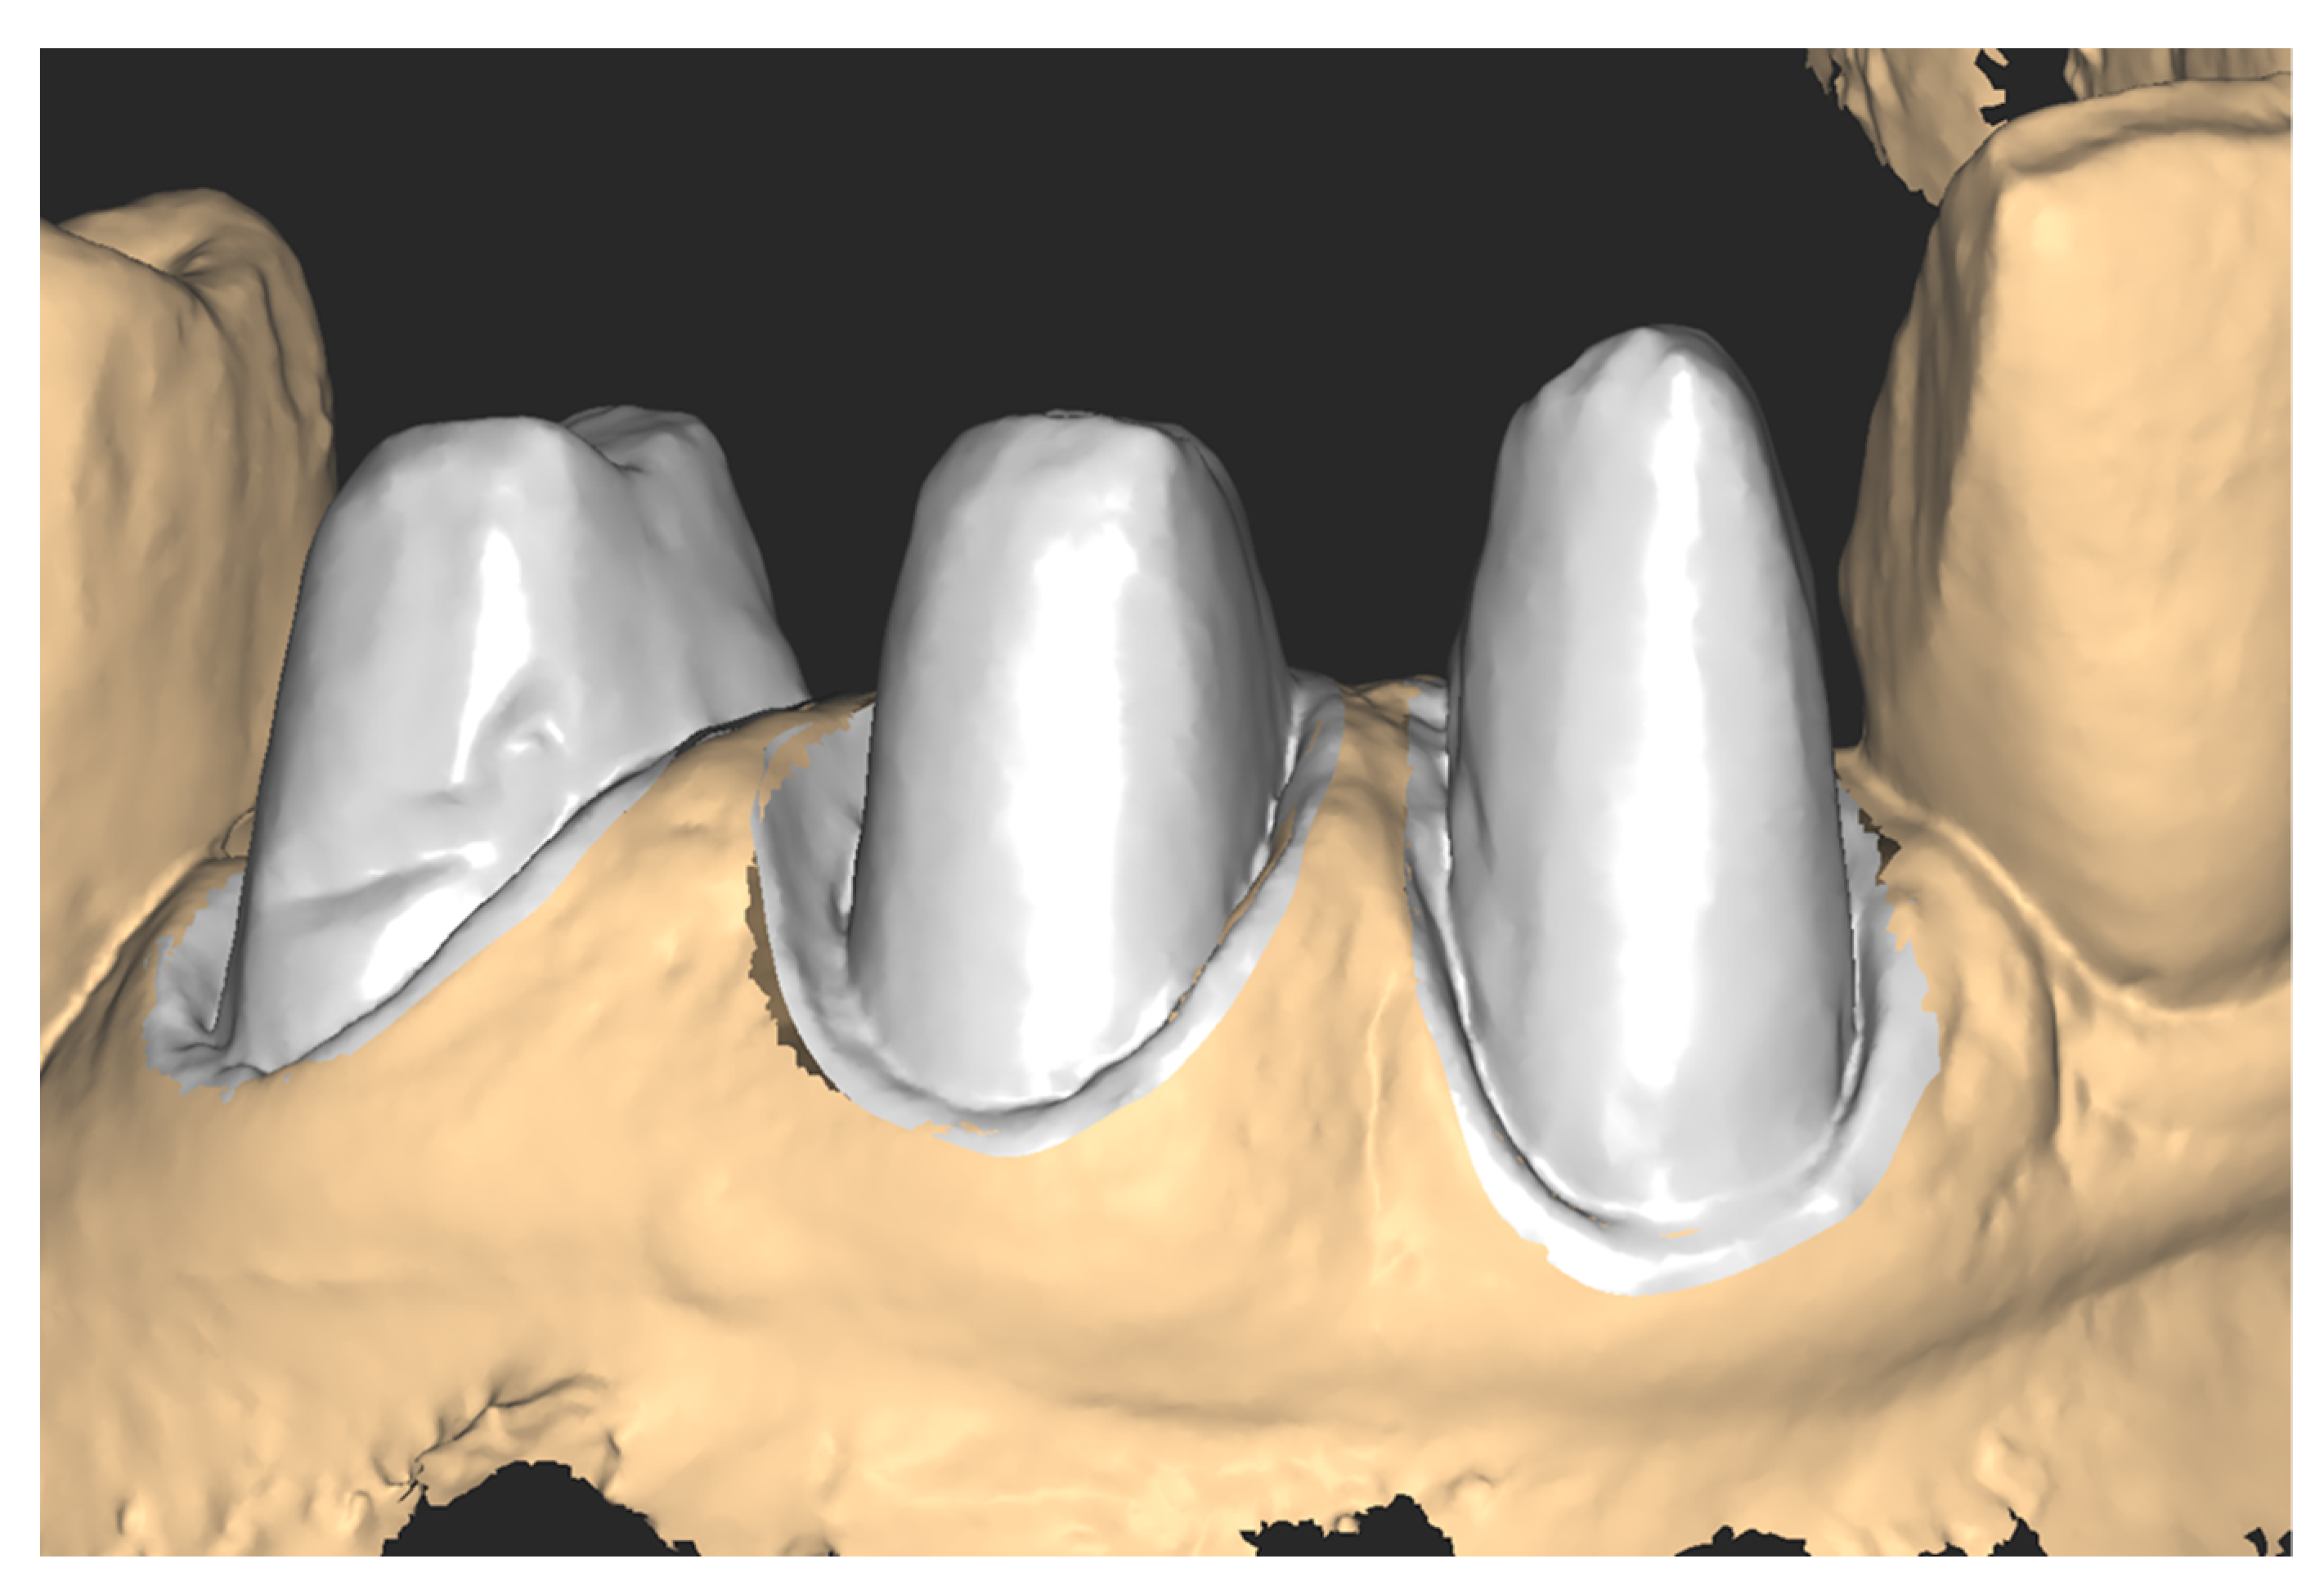

Figure 15.

Substitution of the digital abutments on the master model.

Figure 16.

Modelling the zirconia crowns.

To further detail the workflow and to serve as a proof-of-concept clinical case, crowns were designed and milled from 1200 MPa zirconia blocks (Dental Direkt, Spenge, Germany). To test ex vivo the fitting of the zirconia crowns, a master model was printed using a Form 2 printer (Formlabs, Somerville, MA, USA), and the resin “Model” with accuracy on the z-axis set to 25 µm.

The crowns obtained were judged for clinical fit by a clinician (Figure 17). The rate of compression of sulcular tissues was good. A radiographic control taken after luting showed a proper fit (Figure 18).